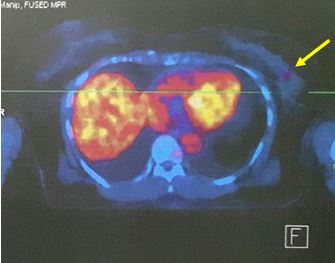

Chúng tôi đã tiến hành chụp PET/ CT đánh giá giai đoạn trước điều trị kết quả cho thấy hình ảnh khối u vú trái vị trí ¼ trên ngoài tăng hấp thu 18F- FDG, không phát hiện thấy các tổn thương di căn tại cơ quan khác.

Hình 2. Hình ảnh tổ chức u tăng hấp thu 18F- FDG vị trí ¼ vú trái trên ngoài (mũi tên đỏ)